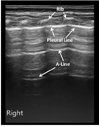

新生儿正常肺组织在超声下呈低回声,胸膜线与A-线均清晰显示,呈光滑、清晰、规则的高回声,二者与等间距平行排列;实时超声下肺滑清晰存在,无或可有少数几条B线;但无胸腔积液、肺实变(图1)。

注:MAS:胎粪吸入综合征;A:探头与肋骨垂直扫描;B:探头与肋骨平行扫描 MAS:meconium aspiration syndrome;A:the probe was perpendicular to the ribs;B:the probe was parallel to the ribs